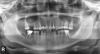

VampKill Опубликовано 26 августа, 2008 Поделиться Опубликовано 26 августа, 2008 Выбирать нужно врача, а не название имплантата. А врач сам разберется что в Вашем случае необходимо делать. Спасибо за ответ. С врачем вот пока все и не определюсь. Есть предложение от одной клиники с XiVe имплантанции (циркониевый абатмент, коронка церкониевая)x2 штуки, наращивание кости + лечение 1 зуба (возможный периодонтит), + удаление того зуба что рядом с удаленным, ну и на 3 зуба вставки из золота с циркониевыми коронками. и все это за 380к деревянных. И второе предложение от знакомого с Альфа-Био, все остальное он говорит такое-же, но за 225к деревянных (и как он мне сказал что альфа-био из той же качественной категории). И что-то я уже во всем запутался... Может посоветуете более детально? Снимок внизу. (мост стоит на клыке, на двух передних и следующий после него зуб, вот этот мост и убирается) Ссылка на комментарий